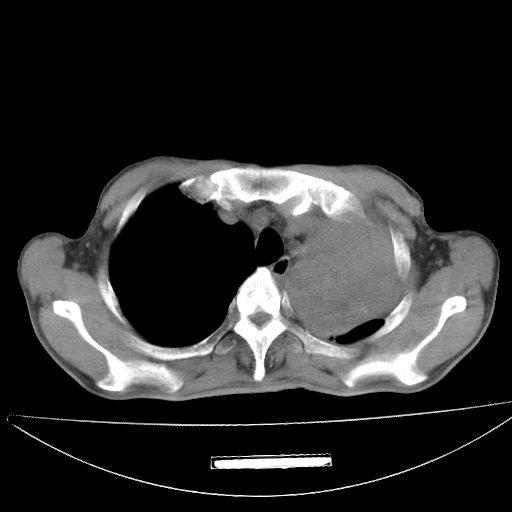

以下是引用杀毒软件在2009-4-28 17:58:00的发言:[br]考虑----左肺慢性肺脓肿形成继发上叶含气不良---抗炎后复查---待排肿瘤所致[br][br][本贴已被 杀毒软件 于 2009-4-28 18:01:26 修改过]